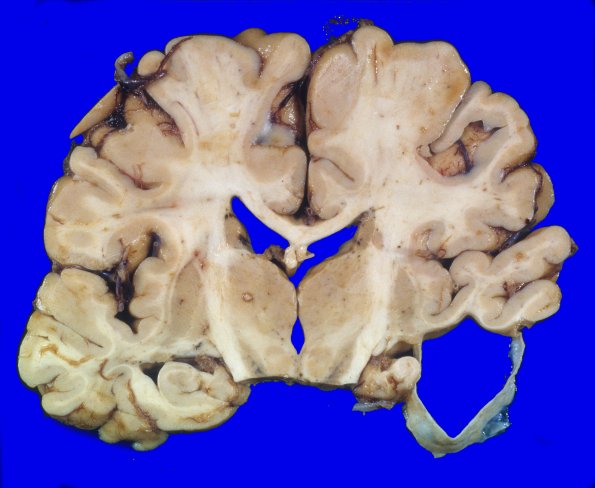

11A3,4 Although some arachnoid cysts typically have a benign relationship with the underlying brain, in this case there is loss of temporal cortex, the underlying white matter and atrophy of adjacent hippocampal cortex.